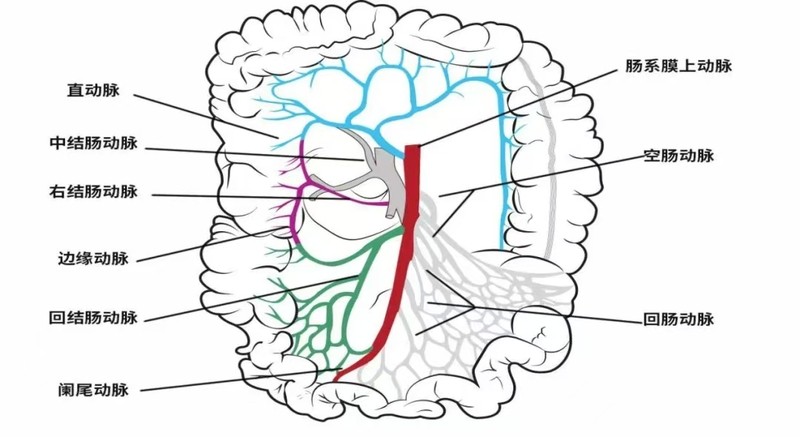

肠系膜上动脉栓塞(SMA),由于发病初期临床症状不典型,被称为腹痛中的隐形杀手。 要想深入了解这种疾病发生的原因,让我们一起看一下肠系膜上动脉的解剖。肠系膜上动脉从腹主动脉前壁发出(见图一),沿途向左侧发出十几条肠动脉(见图二),它们分布于十二指肠、胰头、空回肠、盲肠、升横结肠等腹腔内广泛的供血区域。

图一 肠系膜上动脉从腹主动脉前壁发出的具体位置

图二 肠系上膜动脉(红色)发出的动脉血管分支(其他彩色血管)

其次,由于肠系膜上动脉的主干开口较大,并与腹主动脉呈倾斜的夹角(见图一),所以栓子可能顺着血流方向,比较容易的进入肠系膜上动脉,从而造成肠系膜上动脉栓塞。临床上,肠系膜上动脉栓塞占肠系膜血管缺血性疾病的一半左右。 可见栓子是引发肠系膜上动脉栓塞的罪魁祸首,那么这些血栓来自哪里?一般来说,有三种来源: